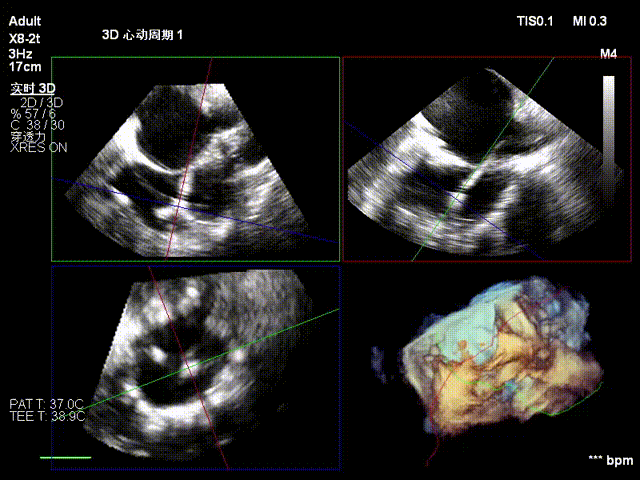

经右颈内静脉穿刺建立通路,置入18Fr鞘管,将K-Clip®输送系统送达右心房。依托三维经食管超声心动图(3D TEE)联合 DSA 双模态引导,经验精准定位瓣环,于后隔交界(P-S commissure)植入14T规格K-Clip®,前后交界(A-P commissure)植入16T规格K-Clip®,实现瓣环多点精准环缩。每枚夹子释放后,团队实时通过超声评估瓣叶对合及反流改善情况,严格遵循 “精准定位 - 锚定验证 - 安全解离” 的规范化操作流程,确认无瓣叶损伤、瓣口狭窄及心包并发症后,完成器械解离与撤出。

1. 术中基线评估三尖瓣反流程度